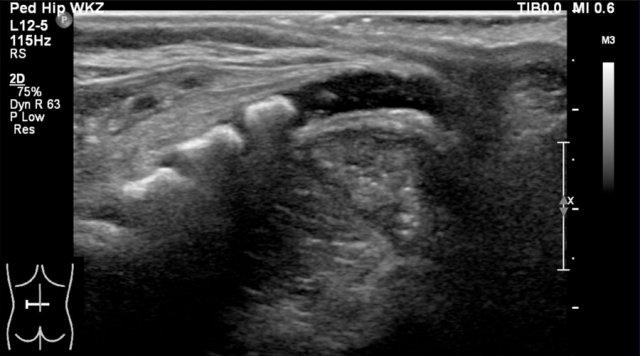

Đầu dưới của tủy phình to, đó là phình tủy thắt lưng.

Tủy thon dần thành một hình nón nhọn (mũi tên xanh).

Đuôi ngựa được quan sát như một bó các sợi di động.

Nếu trẻ nằm ở tư thế nghiêng, các sợi sẽ lắng xuống phía sau theo trọng lực.

Nếu trẻ được khảo sát ở tư thế nằm sấp với gối kê dưới bụng, các sợi sẽ di chuyển về phía bụng.

Filum terminale có thể được nhìn thấy như một sợi tăng âm mảnh.

Túi màng cứng kết thúc ở khoảng mức S2.

Phía xa hơn là mô mỡ.